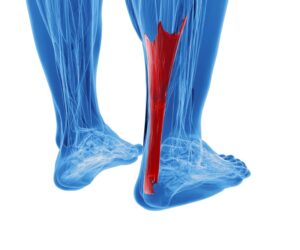

רצועות הקרסול הן רקמות חיוניות ליציבות התנועה ולהגנה על המפרק, אך יש להן נקודת תורפה משמעותית – אספקת הדם אליהן מאוד מוגבלת. משמעות הדבר היא שתהליכי הריפוי בקרסול נמשכים זמן רב, ולעיתים אף אינם מתרחשים באופן טבעי ומלא. אחת הפציעות השכיחות בקרב ספורטאים ואנשים מהשורה היא קרע ברצועה בקרסול – מצב שעלול להפוך לבעיה כרונית אם לא מטפלים בו נכון. כיום יש דרך לעודד את הגוף לרפא את עצמו, ללא ניתוחים מיותרים או תרופות, ולהוביל אותו להחלמה טבעית ויעילה במיוחד.

הרצועות הן גמישות אך חזקות, מחברות בין עצמות הקרסול ותומכות ביציבות המפרק. כאשר הקרסול עובר תנועה חדה ולא טבעית, כמו סיבוב פתאומי או נחיתה לא טובה – הרצועות עלולות להימתח יתר על המידה או להיקרע.

ישנם שלושה סוגים עיקריים של פגיעות ברצועה:

- מתיחה – פגיעה קלה, לרוב חולפת במהירות.

- קרע חלקי – חלק מסיבי הרצועה נפגע.

- קרע מלא – הרצועה נקרעת לגמרי ואינה יכולה לבצע את תפקידה.